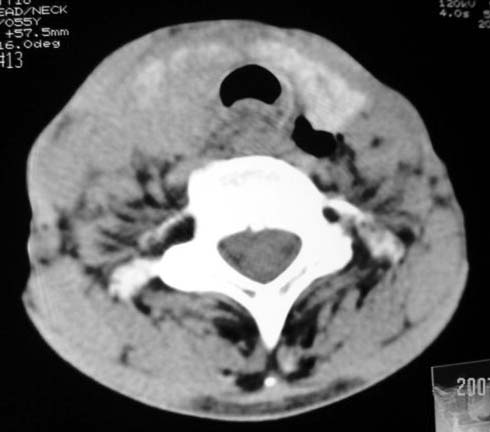

以下是引用dyqct在2007-4-20 16:19:00的发言:[br]考虑:1、左侧梨状窝区破裂伴左颈深、浅部气肿。[br] 2、右侧甲状腺区血肿(请追问病史是否伤及右颈部)。[br] 3、建议病情稳定后增强扫描除外右侧甲状腺腺瘤。